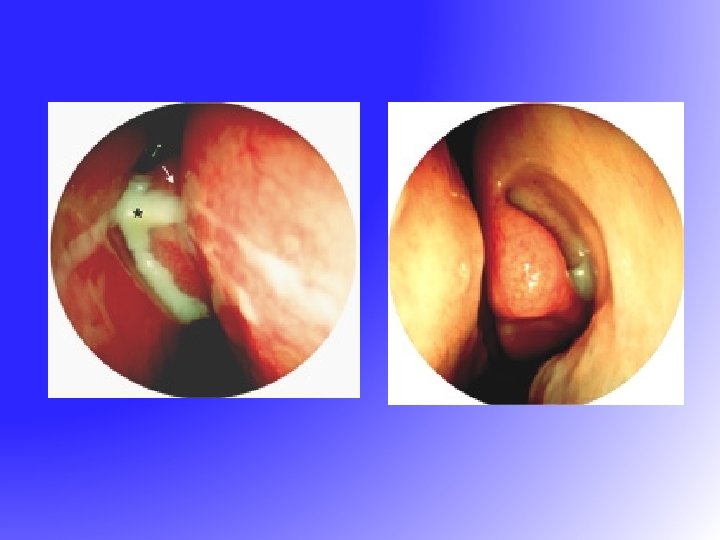

FESS • Functional Endoscopic Sinus Surgery – resume the normal function of sinus • drainage • ventilation • Messerklinger 1960 s – sinus mucus drain in a genetically determined path to the natural ostium

FESS • Functional Endoscopic Sinus Surgery – resume the normal function of sinus • drainage • ventilation • Messerklinger 1960 s – sinus mucus drain in a genetically determined path to the natural ostium

Post FESS

Post FESS